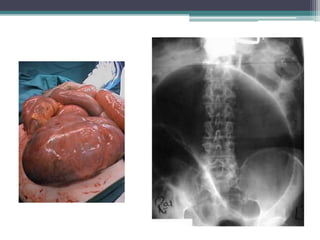

Tài liệu bàn về tắc ruột, bao gồm định nghĩa, phân loại và nguyên nhân của tình trạng này, với sự phân biệt giữa tắc cơ học và cơ năng. Các triệu chứng và chẩn đoán lâm sàng được trình bày, kèm theo phương pháp chẩn đoán cận lâm sàng như x-quang và siêu âm. Ngoài ra, tài liệu cũng đề cập đến các biến chứng và hậu quả của tắc ruột.